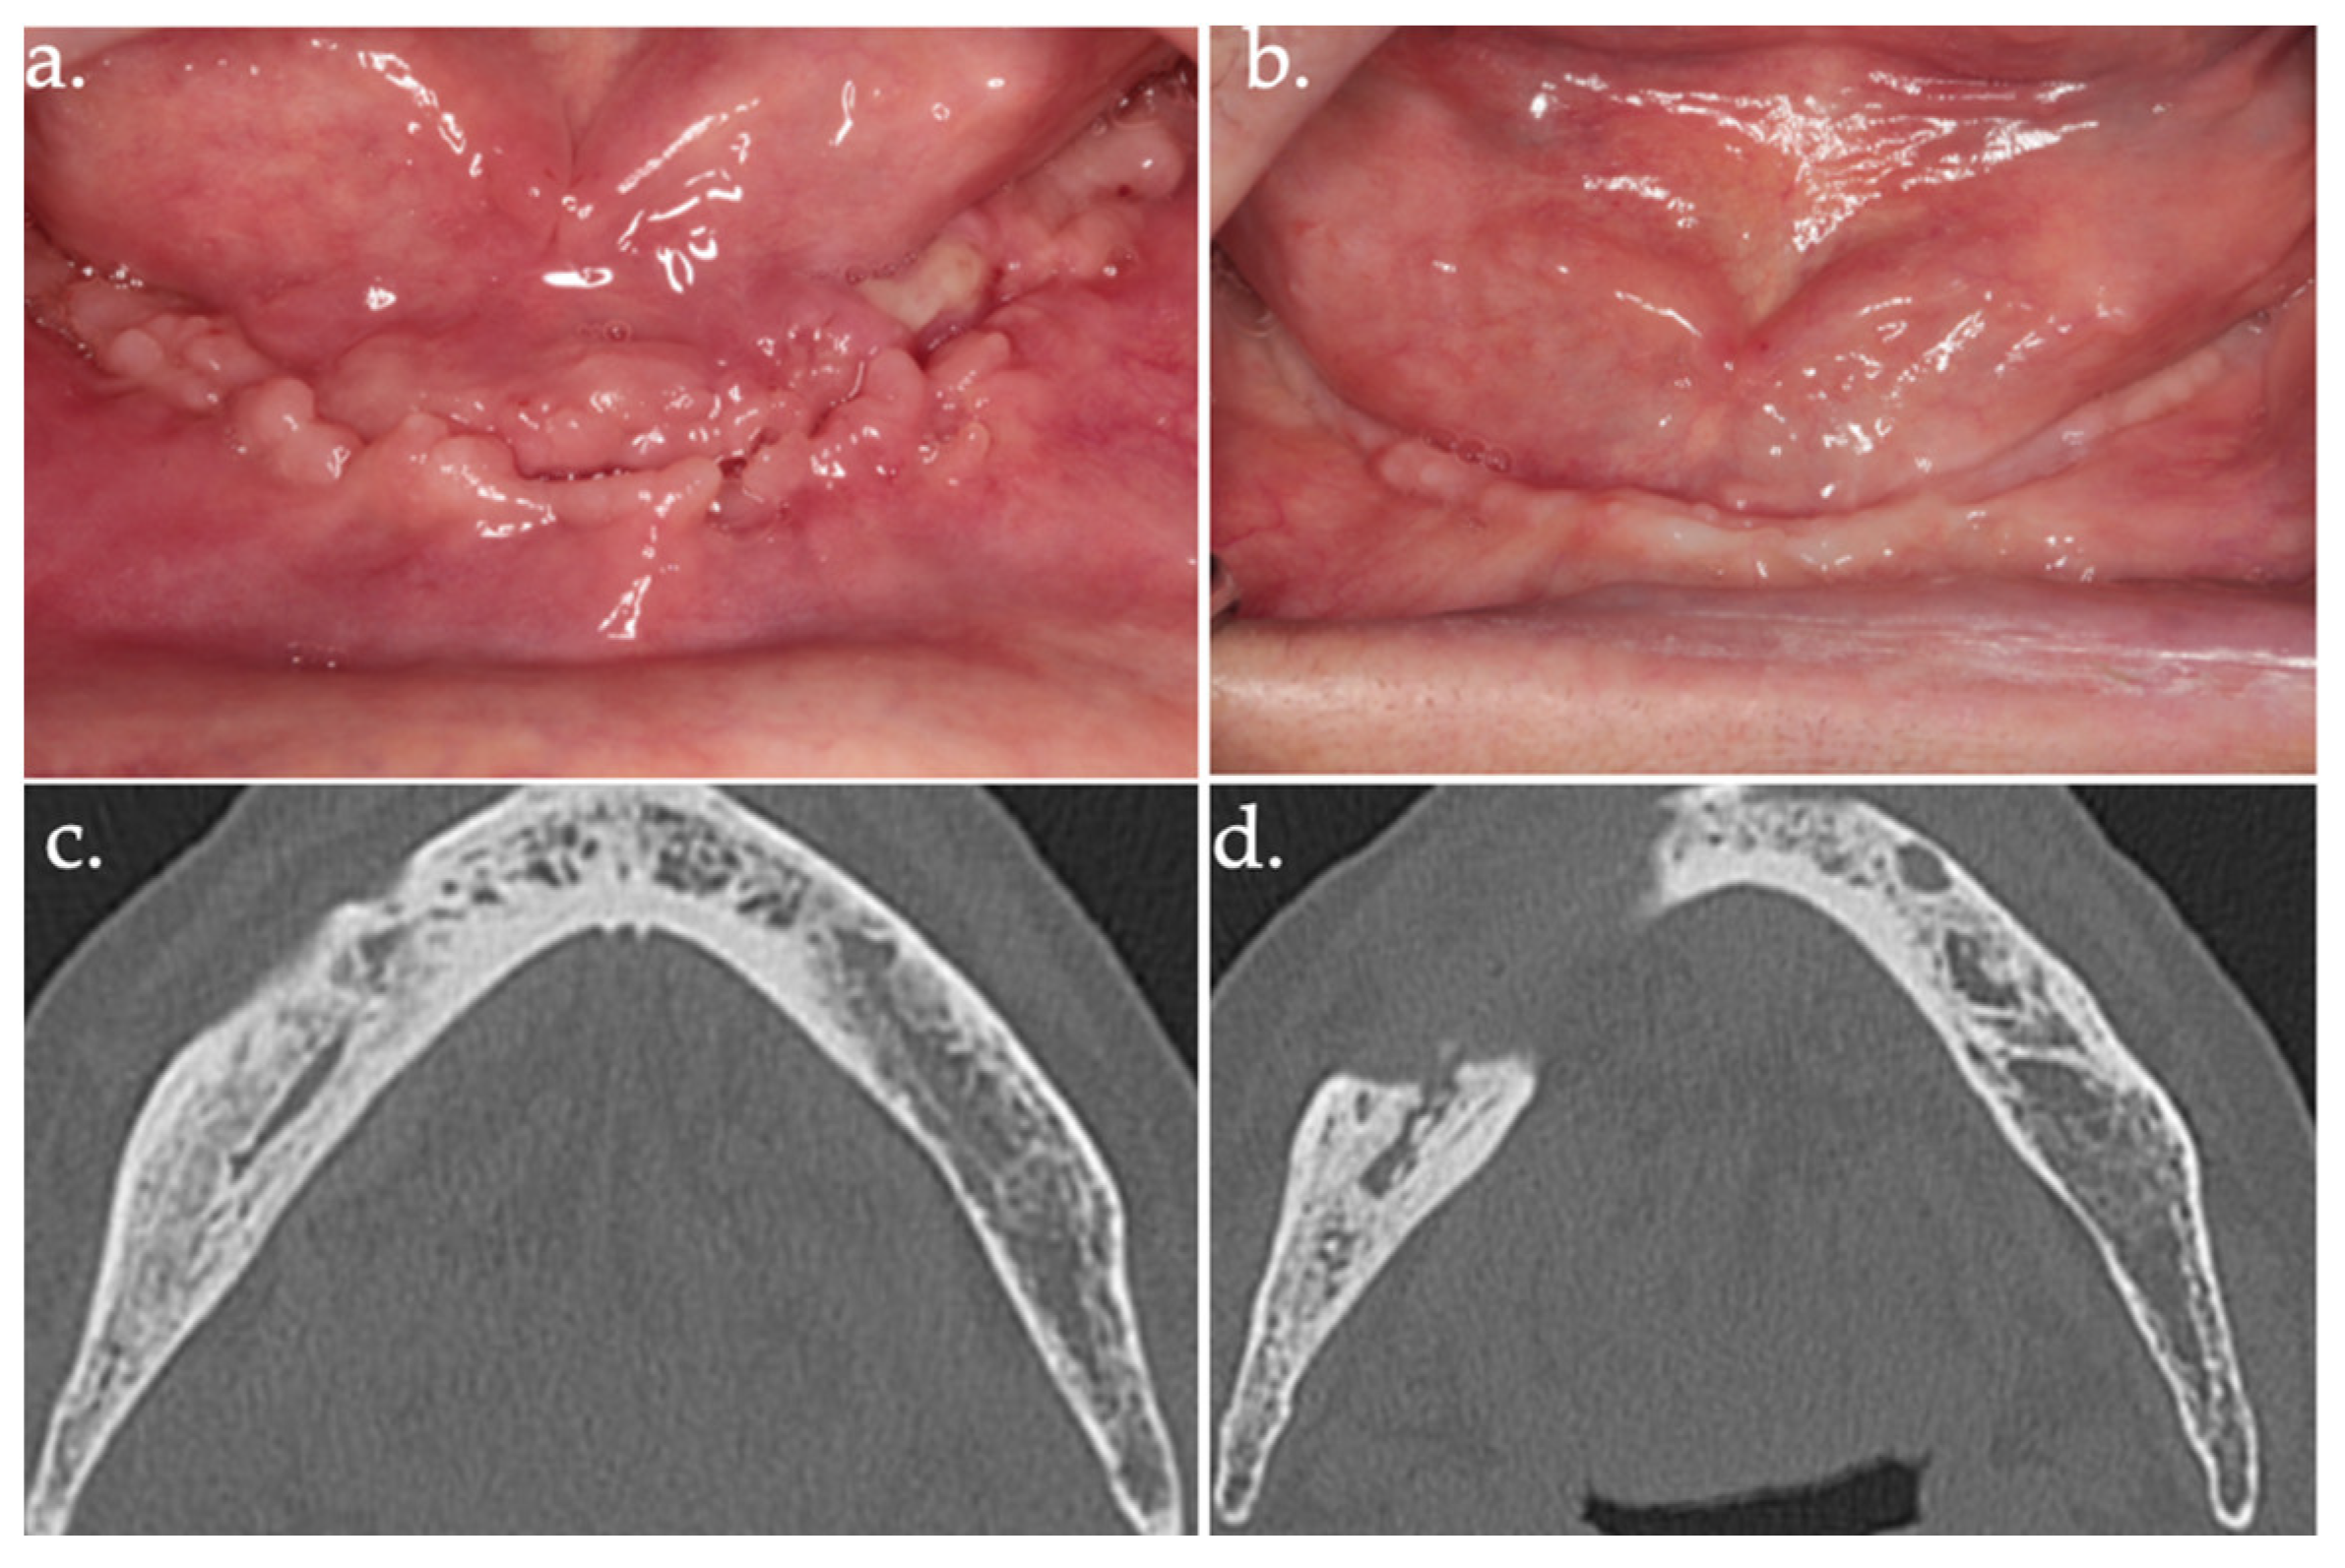

3.2. Clinical Outcomes of Surgical Intervention

3.3. Histopathological Findings